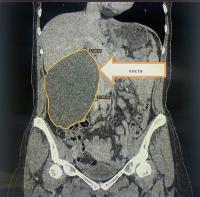

В урологическое отделение Коломенской больницы поступила 52-летняя пациентка с сильными болями в правой половине живота. При пальпации врачи обнаружили значительное по размерам новообразование, а при проведении компьютерной томографии была выявлена гигантская киста правой почки размером 17 х 11,5 см, занимавшая практически половину брюшной полости. Из-за своих размеров новообразование зажало и деформировало правую почку.